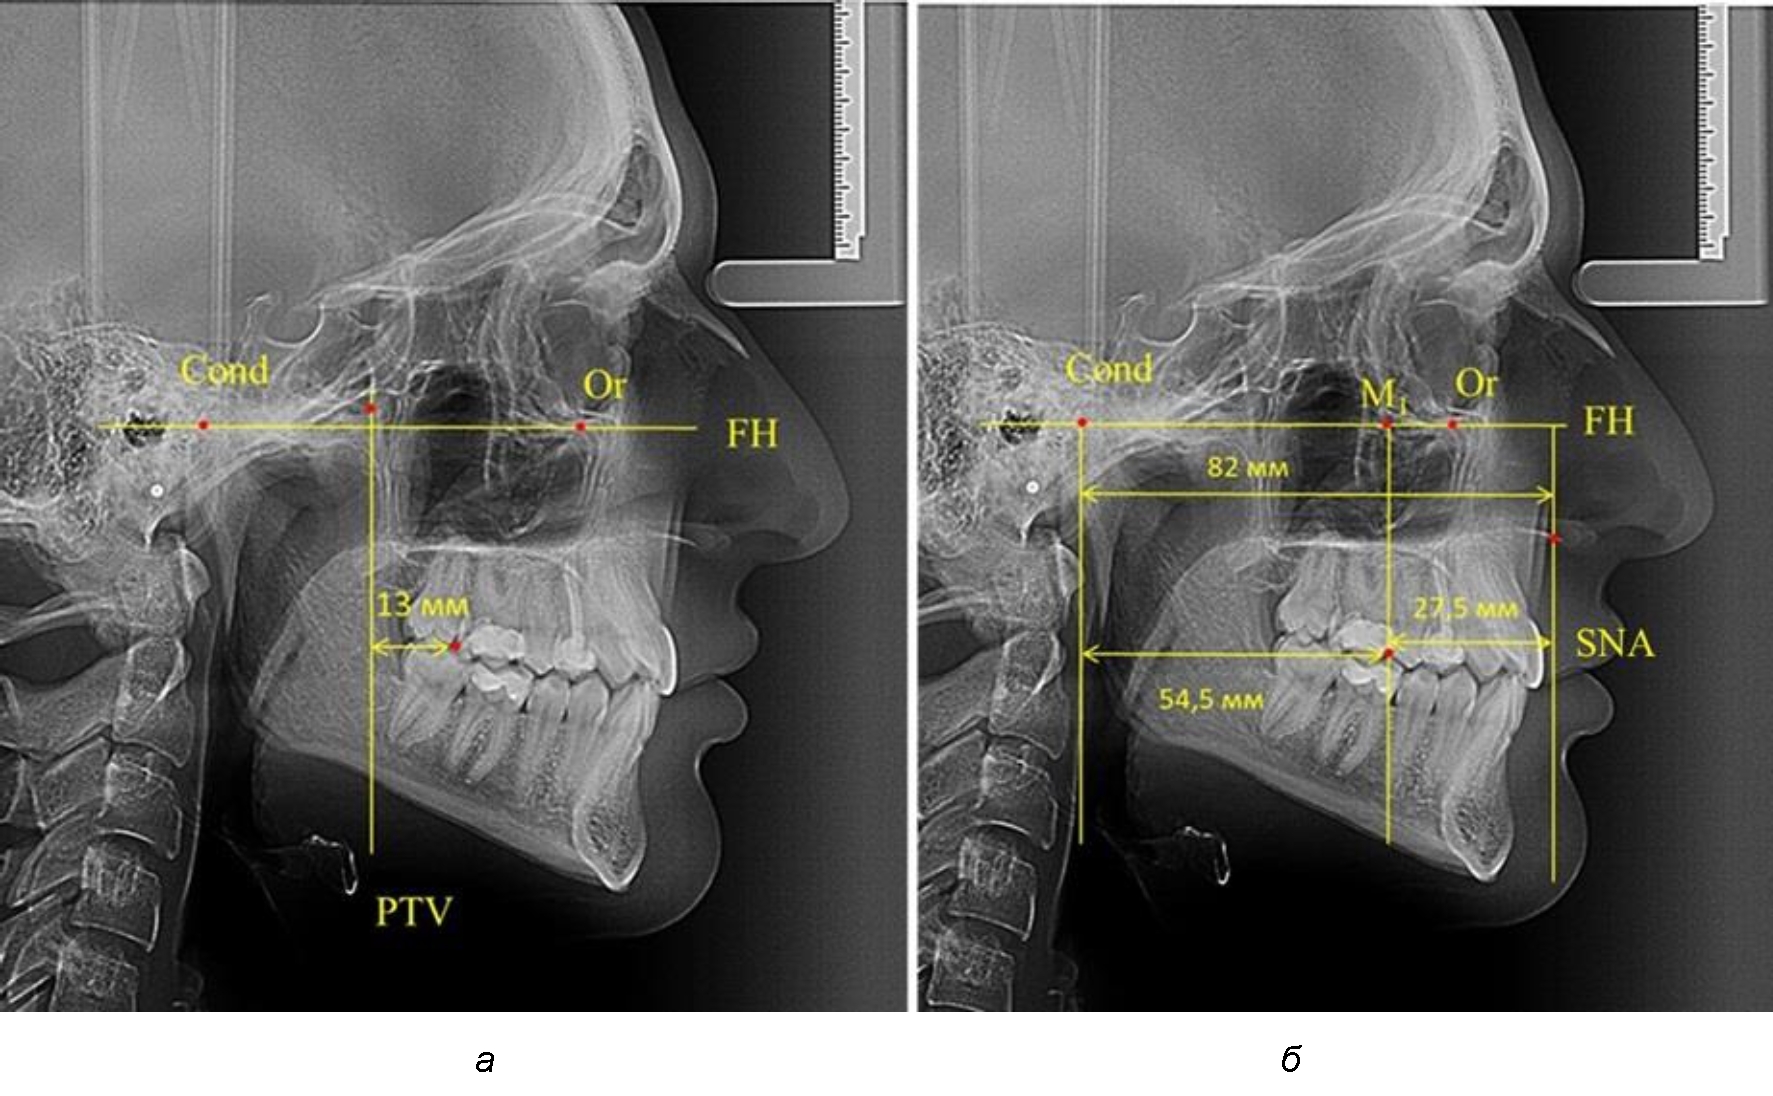

После прорезывания вторых постоянных моляров кондилярно-спинальный увеличивался до 80 мм.

Дистальная поверхность первого постоянного моляра отстояла от крыловидной вертикали на величину, составляющую около 18 мм, что, так же, как и в предыдущих периодах прикуса, было близким по значению к данным R. E. McDonald, а именно возраст, плюс 3 мм.

Обращает на себя внимание отношение глубины гнатического отдела лица к дистальному отделу, а именно к кондилярно-молярному расстоянию, которое, вне зависимости от сагиттальных размеров, составляло 1 : 1,5.

Рентгенограмма 16-летнего ребенка, с реперными линиями и анализируемыми линейными параметрами по двум используемым методам, представлена на рис. 6.

Рис. 6. Особенности положения первых моляров по R. E. McDonald (а) и по предложенному методу (б) у ребенка 16 лет